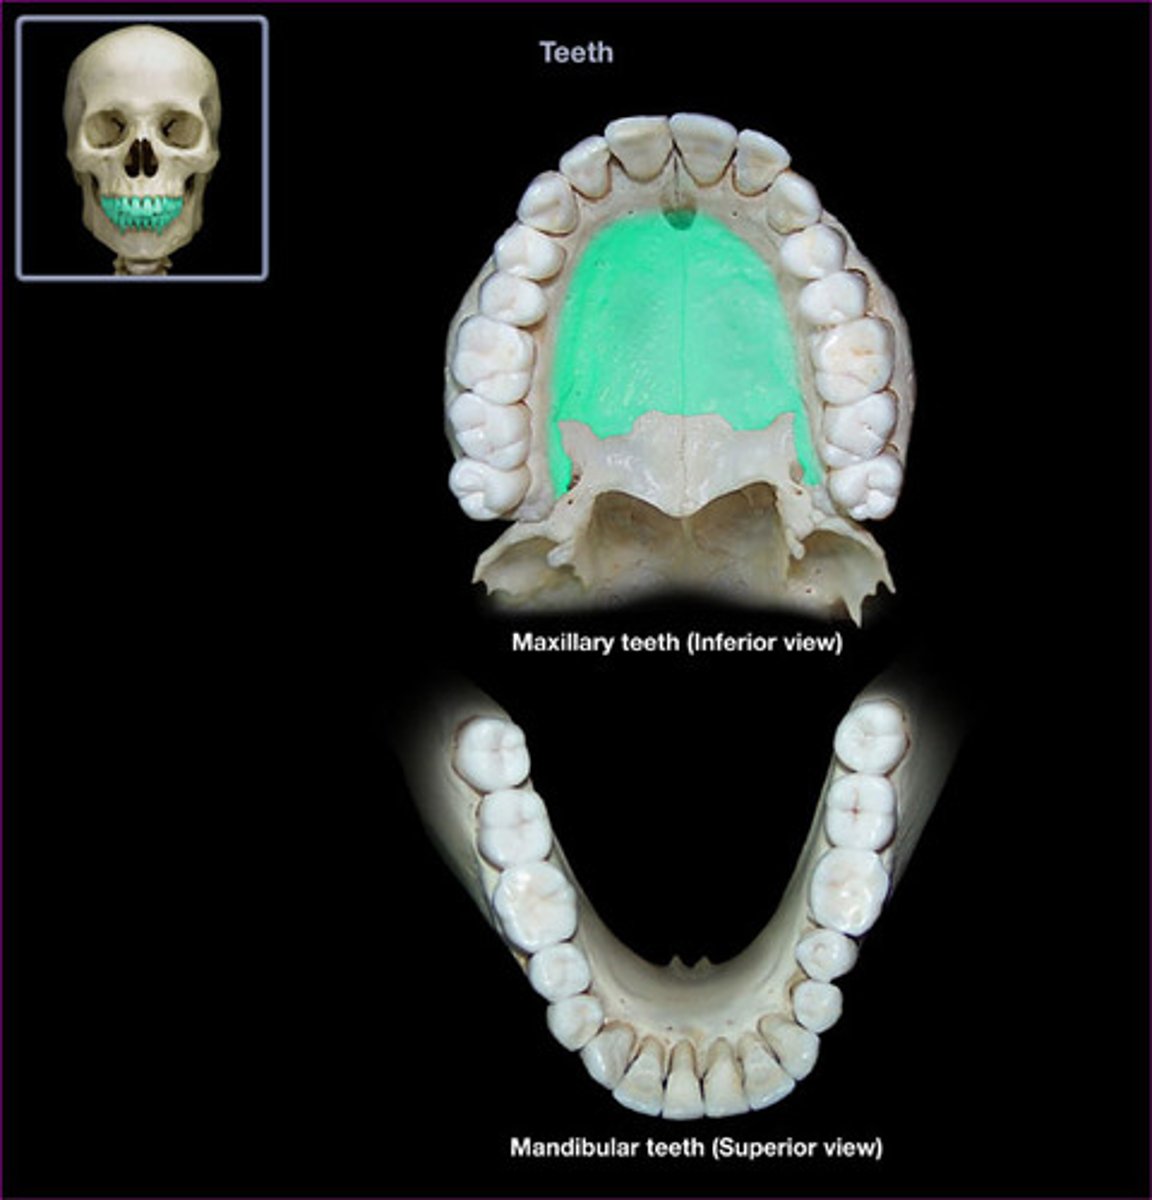

Submentovertical (SMV)

- Pt is seated/ recumbent supine / place vertex on grid/ IOML is parallel to IR

- Perp to the IOML ,( 1" posterior to the outer canthus)

- Zygomatic arches free of superimposition/ mandible/vomer/maxillae (palatine process)/ No rotation of the head

What is this projection?

How is Patient positing?

What is the CR?

What are the structures shown?